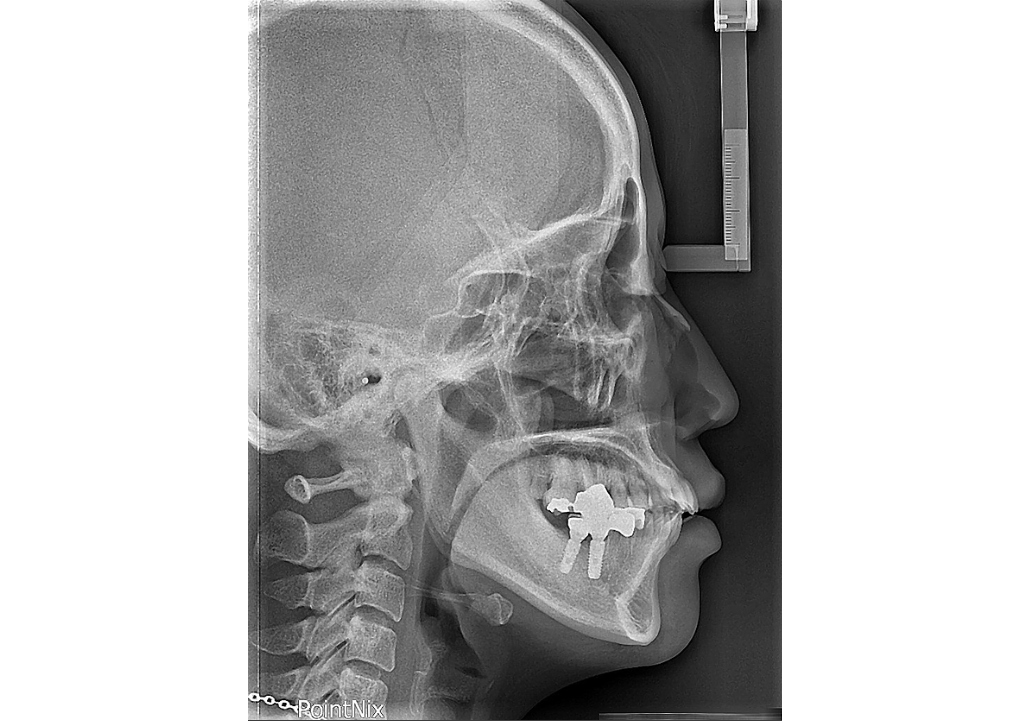

T.M.J